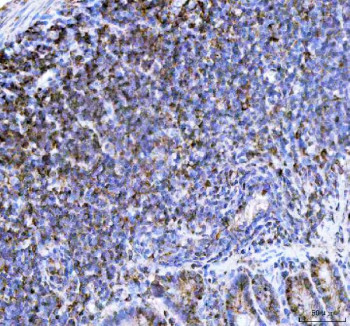

Adding 0.2 ml of distilled water will yield a concentration of 500 ug/ml. The NCF1 antibody targets Neutrophil cytosolic factor 1, a cytoplasmic component of the NADPH oxidase complex responsible for generating reactive oxygen species (ROS) during immune responses. Encoded by the NCF1 gene, this protein, also known as p47phox, acts as an organizer subunit that bridges cytosolic oxidase components with the membrane-bound catalytic core. The NCF1 antibody is a vital reagent for understanding how oxidative bursts are initiated in phagocytes and how these processes regulate host defense, inflammation, and redox signaling.Neutrophil cytosolic factor 1 becomes phosphorylated upon cellular activation, prompting its translocation to the plasma membrane where it associates with p22phox, gp91phox (CYBB), and other subunits to assemble the active NADPH oxidase complex. This enzymatic system produces superoxide radicals essential for microbial killing. The NCF1 antibody enables detection of this phosphorylation-dependent activation and helps identify conditions that modulate oxidase assembly.Genetic defects in NCF1 lead to chronic granulomatous disease (CGD), a primary immunodeficiency characterized by recurrent infections due to defective superoxide generation. In such patients, mutations often cause reduced or absent p47phox expression. Using the NCF1 antibody, researchers can distinguish functional versus nonfunctional protein forms, aiding in diagnostic and mechanistic studies of CGD. Beyond innate immunity, Neutrophil cytosolic factor 1 also contributes to redox-dependent signaling in endothelial and neuronal cells, highlighting its importance beyond phagocytes.The NCF1 antibody is suitable for western blotting, immunoprecipitation, and flow cytometry, where it detects both total and phosphorylated protein forms. Its applications extend to studies examining oxidative stress, cell signaling cascades, and inflammatory pathway regulation. Because NADPH oxidase activity affects vascular tone, apoptosis, and cytokine production, NCF1 has broad physiological relevance. The antibody provides a reliable means to quantify expression changes under oxidative or inflammatory stress.In oncology and cardiovascular research, aberrant activation of NCF1-containing complexes has been associated with chronic inflammation and tissue damage. Elevated expression may amplify ROS production, promoting DNA damage and tumorigenesis. Conversely, impaired function can weaken immune defense and tissue repair. The NCF1 antibody offered by NSJ Bioreagents supports detailed exploration of these opposing roles, helping define how redox balance influences health and disease.By providing consistent detection across multiple platforms, the NCF1 antibody remains an essential reagent for studying oxidative metabolism and immune cell function. Its use continues to expand from immunology into neurobiology and cancer biology, where understanding reactive oxygen mechanisms is increasingly central to therapeutic innovation.

| Application: | ELISA, FC, IF, IHC, WB |